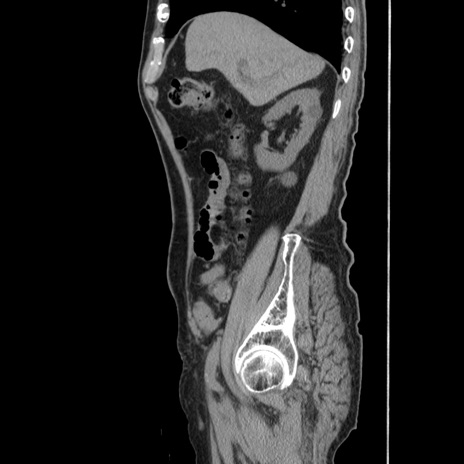

症例24(矢状断像)

【症例】80歳代男性

【主訴】左側腹部痛、嘔吐

【現病歴】本日早朝より左腹部に痛みあり。昼頃嘔吐認めたため、救急要請。

【既往歴】直腸癌(Mile手術)、胆摘

【身体所見】意識清明、BT 35.9℃、BP 221/93mmHg、SpO2 97%(RA) 、腹部:左ストーマ周囲に限局性の腹部膨隆あり。 膨隆部自発痛・圧痛あり・軟。

【データ】WBC 7700、CRP 0.09